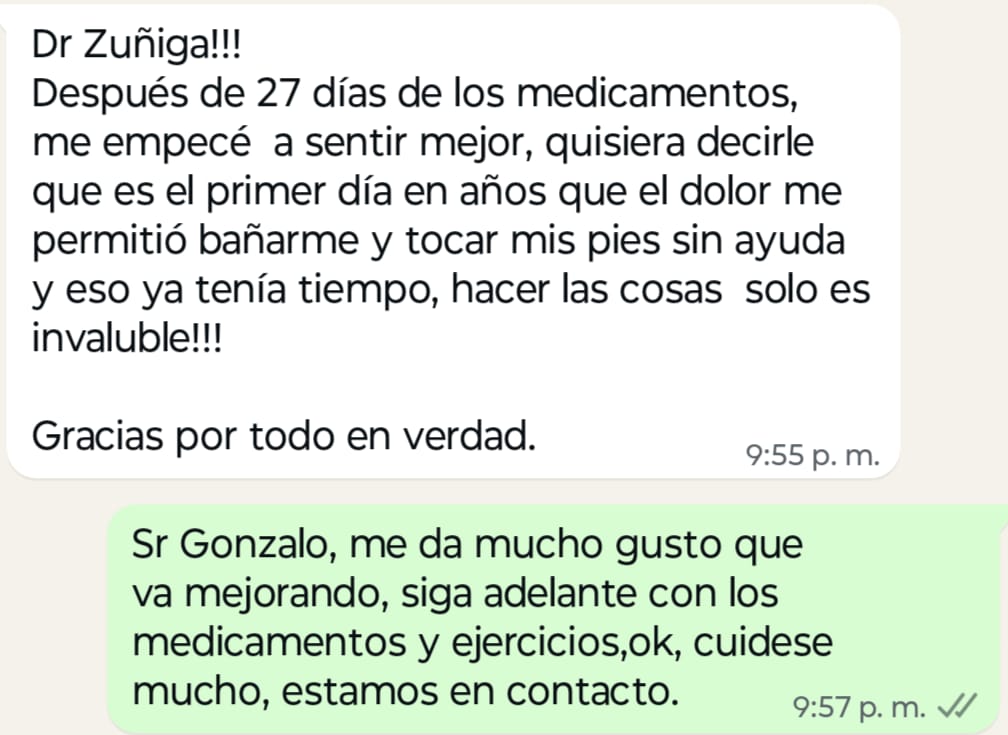

Te ofrecemos una consulta médica especializada para control del dolor crónico y te permita que recuperes tu vida o la de tu familiar o amiga(o).

En la valoración médica, se obtendrá un diagnóstico y la causa por la que se está ocasionando el dolor, se iniciara tratamientos analgésicos tomados vía oral, intramusculares, vía intravenosa o tratamientos potentes por infiltraciones, bloqueos nerviosos guiados por ultrasonido, terapia neural, aplicación de medicamentos bio-reguladores,toxina botulínica, se valorará el inicio de tratamientos para mejorar las emociones como ansiedad, tristeza o enojo. Asociado a tratamientos de rehabilitación física.

Todo ello no solo disminuye el dolor, sino que permite que mejore la fuerza y la movilidad del (a) paciente.

Los conocimientos adquiridos y la experiencia en la docencia universitaria y práctica clínica en hospitales públicos y privados, me han permitido entender y adentrarme en todos los cambios, que se generan en un paciente que padece dolor crónico ( que dura más de 3 meses) y con enfermedades que son amenazantes para la vida; así como los que se generan en el entorno familiar; por un momento hacer empatía con los pacientes, valorar al paciente en su entorno físico, emocional, familiar, laboral y espiritual, brindando el tratamiento más eficaz dependiendo el tipo de dolor y de su intensidad.